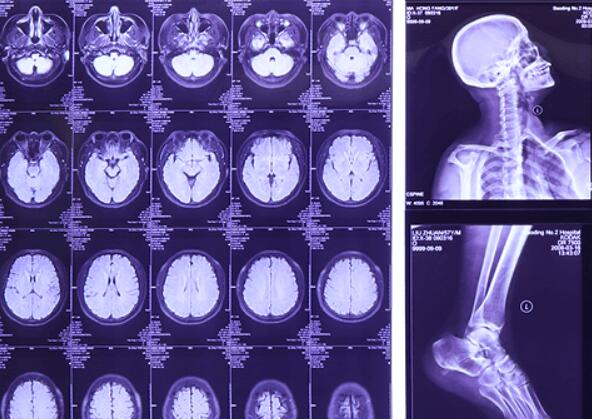

Medical Dry Film

Lucky dry film kx410 uses blue pet as film base with imaging and protective layers coated separately on both sides.The film is fit for thermal printer to print digital image which is processed and stored in the computer to get the various medical images.

Medical Blue&Green X-ray Film

The product is a general green sensitive medical x-ray film, which has green sensitive emulsion layers on both sides of blue polyester base sheet.